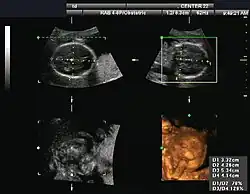

Obstetrical sonography was originally developed in the late 1950s and 1960s by Sir Ian Donald[20][21] and is commonly used during pregnancy to check the development and presentation of the fetus. It can be used to identify many conditions that could be potentially harmful to the mother and/or baby possibly remaining undiagnosed or with delayed diagnosis in the absence of sonography. It is currently believed that the risk of delayed diagnosis is greater than the small risk, if any, associated with undergoing an ultrasound scan. However, its use for non-medical purposes such as fetal "keepsake" videos and photos is discouraged.[22]

Obstetric ultrasound is primarily used to:

- Date the pregnancy (gestational age)

- Confirm fetal viability

- Determine location of fetus, intrauterine vs ectopic

- Check the location of the placenta in relation to the cervix

- Check for the number of fetuses (multiple pregnancy)

- Check for major physical abnormalities.

- Assess fetal growth (for evidence of intrauterine growth restriction (IUGR))

- Check for fetal movement and heartbeat.

- Determine the sex of the baby

An ultrasound result on fetal biometry printed on a piece of paper -